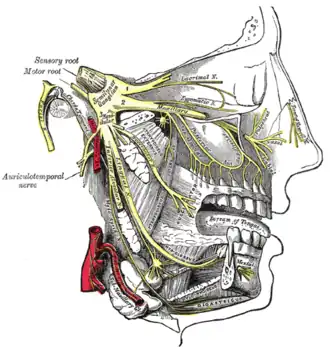

Distribution of the maxillary and mandibular nerves and the submaxillary ganglion

Distribution of the maxillary and mandibular nerves and the submaxillary ganglion -